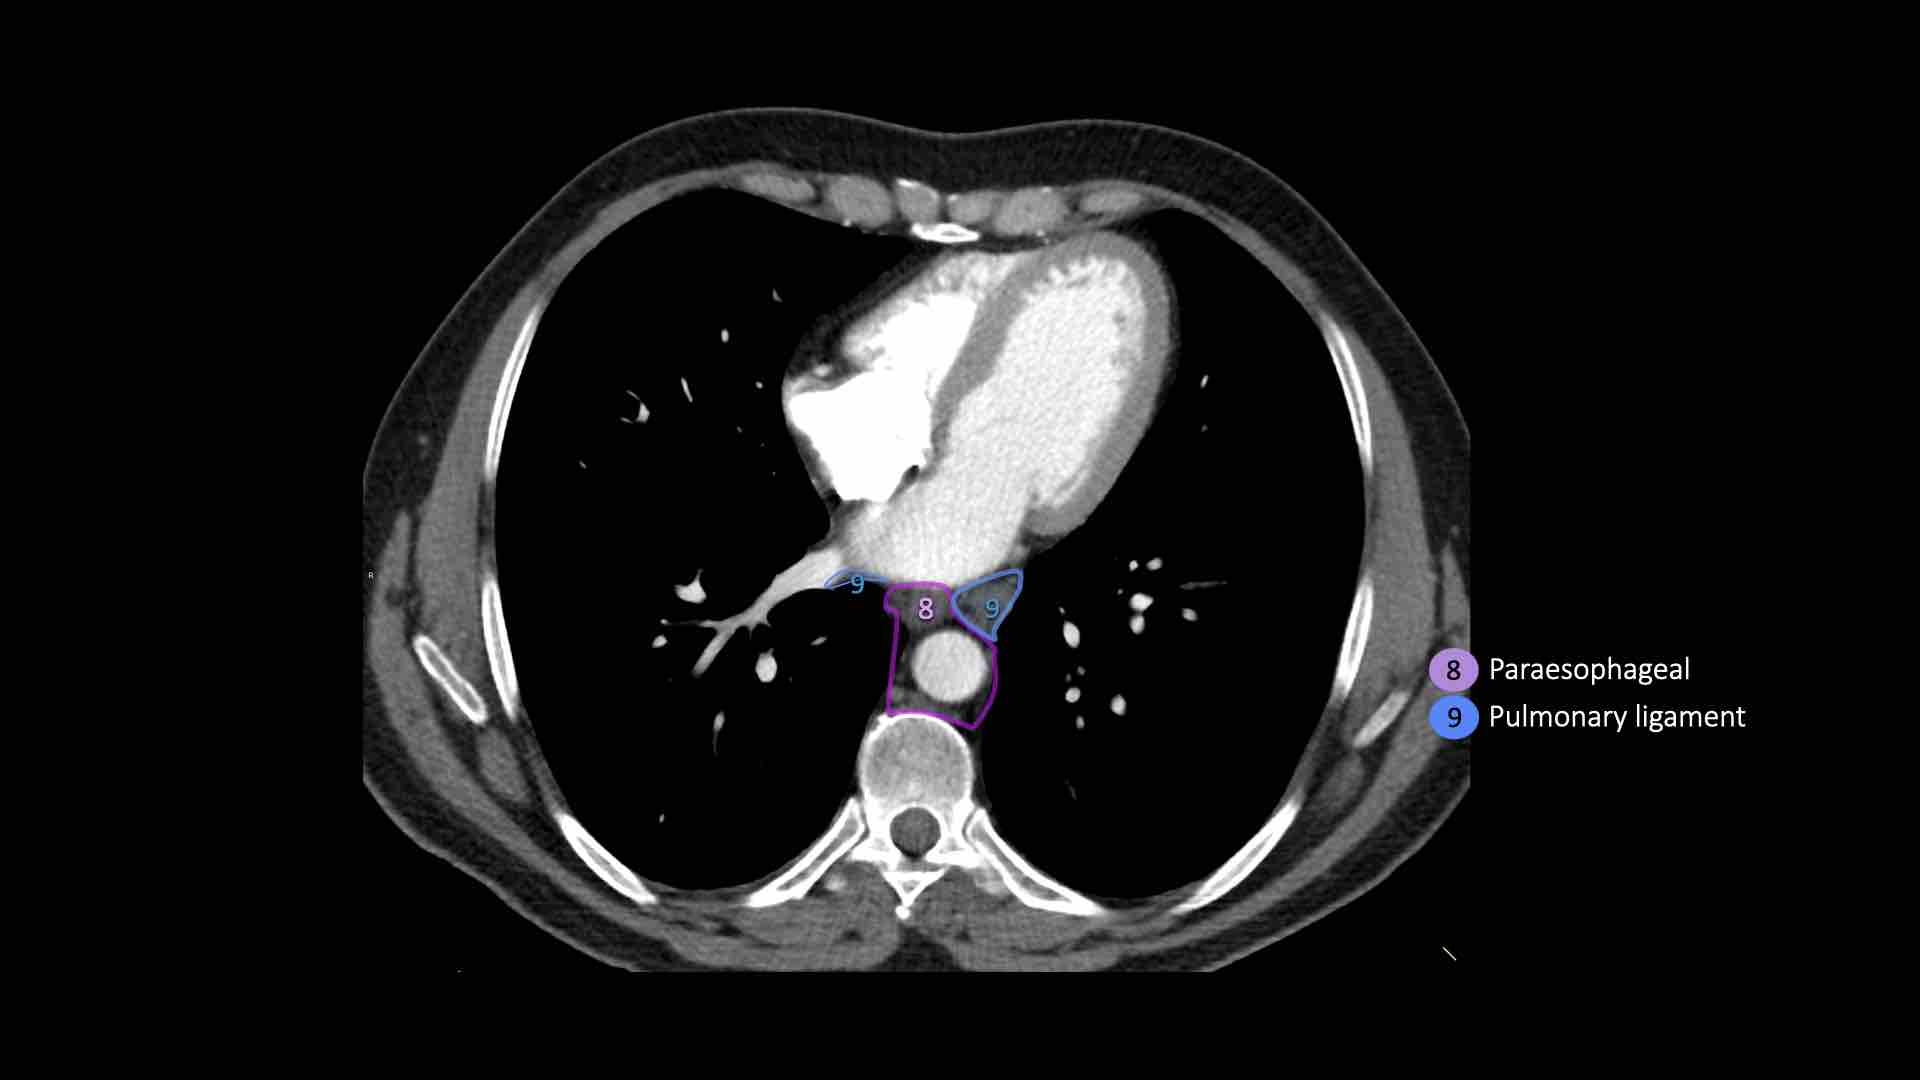

8. Cạnh thực quản

Các hạch nằm dưới carina.

9. Dây chằng phổi

Các hạch nằm trong dây chằng phổi.

8. Hạch cạnh thực quản

Các hạch này nằm bên dưới các hạch dưới carina và trải dài xuống đến cơ hoành.

Bên trái là hình ảnh dưới mức carina.

Bên phải thực quản là một hạch nhóm 8.

9. Hạch dây chằng phổi

Hạch dây chằng phổi nằm trong dây chằng phổi, bao gồm các hạch ở thành sau và phần dưới của tĩnh mạch phổi dưới.

Dây chằng phổi là phần kéo dài xuống dưới của các nếp gấp màng phổi trung thất bao quanh rốn phổi.